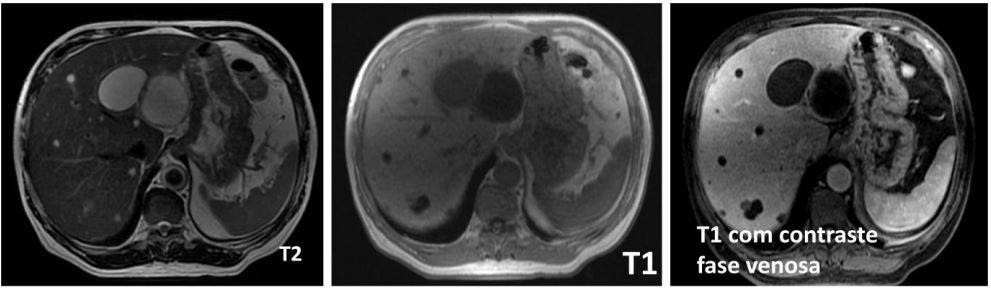

Homem, 46a, acompanhado há um ano devido 2 cistos simples hepáticos em segmentos II e III, de 2,3cm e 3,1cm, respectivamente. Seis meses após, iniciou quadro de desconforto abdominal, adinamia, com piora progressiva, nos últimos 10 dias e perda ponderal de 1,5kg neste período. Apresenta os seguintes exames laboratoriais: Hb= 12,7g/dl; Leucócitos= 16.500mm3 , com 2% de bastões; Plaquetas= 524.000mm3 ; Bilirrubinas total= 0,9 mg/dL; Albumina= 3,9mg/dL; Fosfatase alcalina= 149U/L ; Gamaglutamiltransferase= 223U/L; AST= 56U/L; ALT= 89 U/L.

Realizou ressonância magnética nuclear (RMN) de abdome com as imagens abaixo: